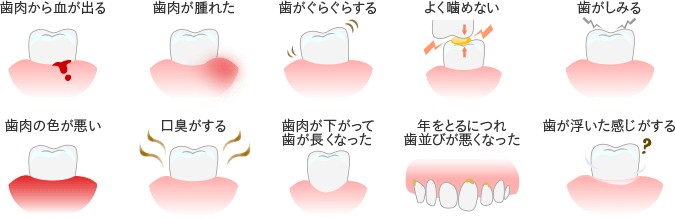

歯周病とはどんな病気かご存知でしょうか?歯周病は歯を失う原因の第一位とされていて、近年では実はむし歯よりも深刻な病気として知られています。

歯周病は初期症状がほとんどないことが特徴で、気がついた時には重症化していることも少なくない恐ろしい病気です。最悪の場合、歯が抜け落ちてしまう可能性もあるため、歯周病は早期発見・早期治療が最も重要となります。

以下のような症状に心当たりのある方は、歯周病の可能性があります。どんなに些細な症状でも、気になる症状がございましたらお気軽にご相談ください。